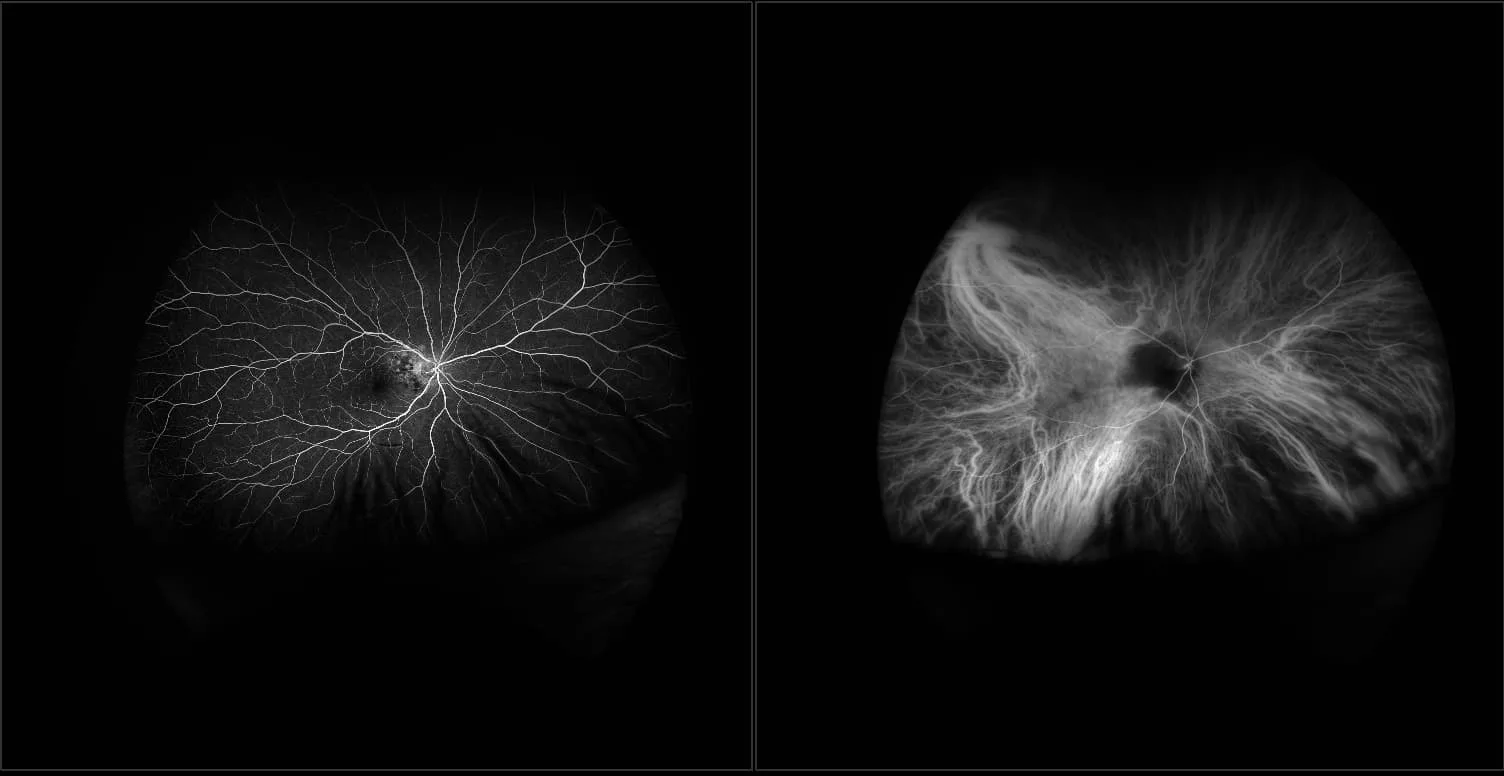

California - Bilateral Peripheral Nevus - Full steer - RG, RGB,